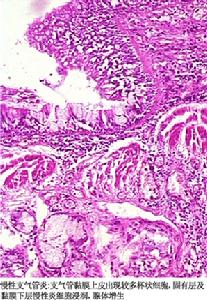

支氣管周圍和肺泡間隔有漿細胞、單核細胞和大量嗜酸粒細胞浸潤,細支氣管粘液腺及杯狀細胞增生,終末細支氣管擴張並有痰液充於其內,有時可以找到真菌菌絲。